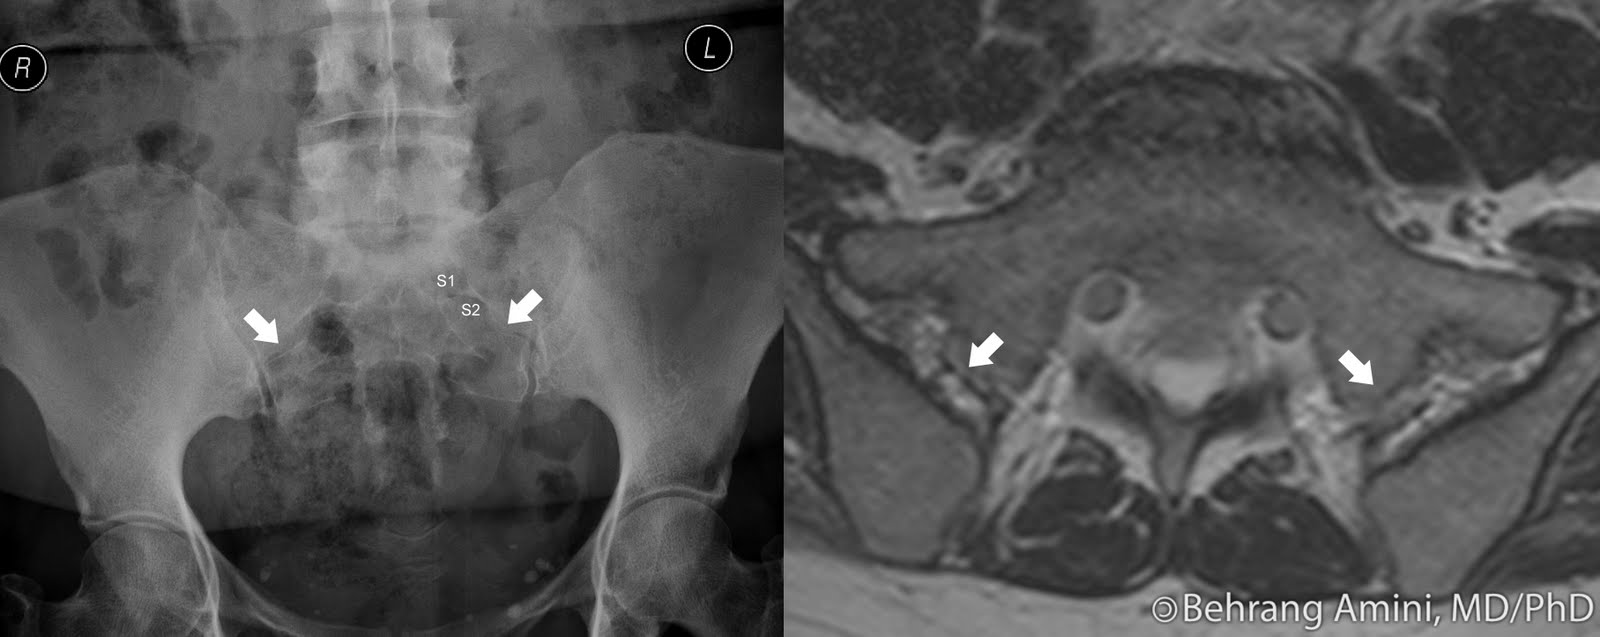

Paget's Disease Sacroiliac Joint . this case demonstrates comorbidity with paget disease and possible ankylosing spondylitis. in this patient, paget’s disease involves both sides of the fused sacroiliac joints with confluent pagetic bone across the joints. as (also known as bechterew disease and marie strümpell disease) is a seronegative spondyloarthropathy, which. Of si joints can be seen in paget disease either unilaterally or bilaterally [10]. sacroiliac involvement in paget's disease leads to joint fusion by cartilaginous destruction and should. specifically, the radiograph of the lumbar and sacral regions showed irregular sclerotic changes of the right. paget’s disease can extend across the si joint leading to ankylosis. Osteoradionecroses also presents as uniform or multiform osteosclerosis.

as (also known as bechterew disease and marie strümpell disease) is a seronegative spondyloarthropathy, which. Of si joints can be seen in paget disease either unilaterally or bilaterally [10]. Osteoradionecroses also presents as uniform or multiform osteosclerosis. sacroiliac involvement in paget's disease leads to joint fusion by cartilaginous destruction and should. specifically, the radiograph of the lumbar and sacral regions showed irregular sclerotic changes of the right. in this patient, paget’s disease involves both sides of the fused sacroiliac joints with confluent pagetic bone across the joints. this case demonstrates comorbidity with paget disease and possible ankylosing spondylitis. paget’s disease can extend across the si joint leading to ankylosis.

Paget's Disease Sacroiliac Joint specifically, the radiograph of the lumbar and sacral regions showed irregular sclerotic changes of the right. Osteoradionecroses also presents as uniform or multiform osteosclerosis. sacroiliac involvement in paget's disease leads to joint fusion by cartilaginous destruction and should. specifically, the radiograph of the lumbar and sacral regions showed irregular sclerotic changes of the right. as (also known as bechterew disease and marie strümpell disease) is a seronegative spondyloarthropathy, which. Of si joints can be seen in paget disease either unilaterally or bilaterally [10]. in this patient, paget’s disease involves both sides of the fused sacroiliac joints with confluent pagetic bone across the joints. paget’s disease can extend across the si joint leading to ankylosis. this case demonstrates comorbidity with paget disease and possible ankylosing spondylitis.